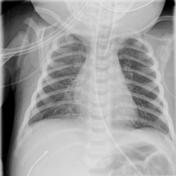

CXR for the case found here:

(CXR source: https://radiopaedia.org/articles/neonatal-pneumonia)